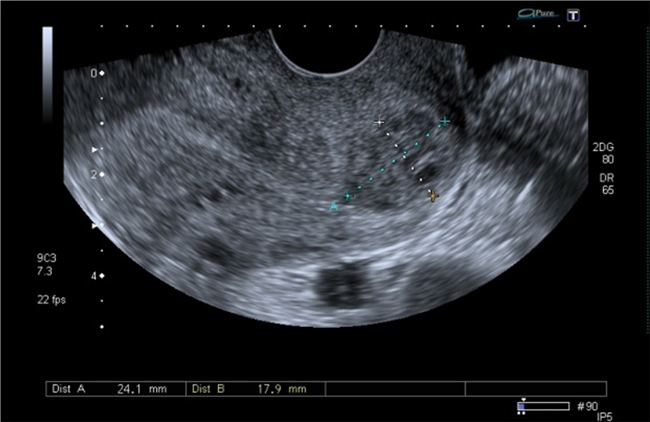

A los dos meses asistió a control y se le realizó una ecografía que mostró la presencia de una imagen hipoecoica heterogénea en la zona del istmo de 2 cm de diámetro en el labio anterior, sin presencia de embrión o saco gestacional (figuras 9 y 10).